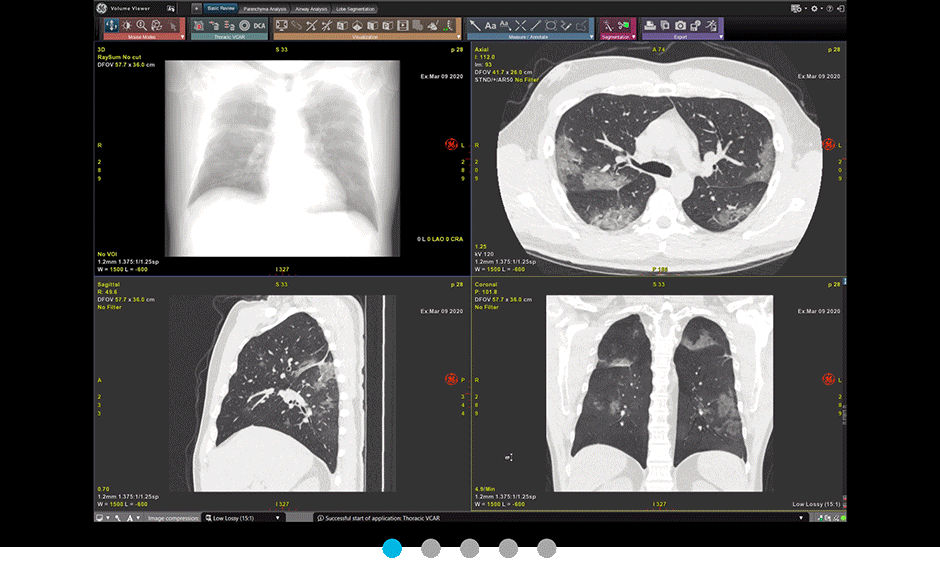

Thoracic VCAR gives you the ability to make quantitative measurements of the lungs to aid in the diagnosis of lung disease. The application blends automated lung and airway segmentation with basic review and advanced lung tissue analysis. Using Thoracic VCAR you can generate a clear, concise report that communicates vital medical information to referring physicians and patients.

Complete reading workflow solution featuring:

• Automated segmentation of lungs and airways

• Individual lobe segmentation and visualization

• Parenchyma analysis with customizable presets to identify different ranges of HU variances within the segmented lung fields

• One-touch 3D airway tracking and automated measurements of wall thickness for airway analysis

• Automatic analysis of GSI pulmonary studies

• Display relative perfusion map based on GSI iodine concentration in lung parenchyma